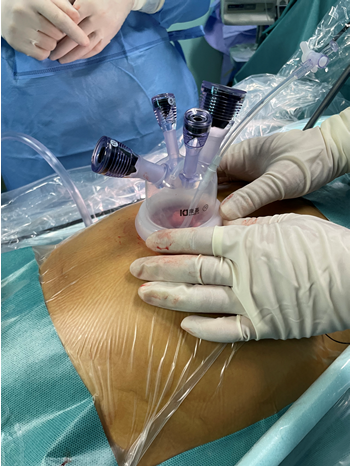

术中使用的一次单孔设备

术中使用的一次单孔设备